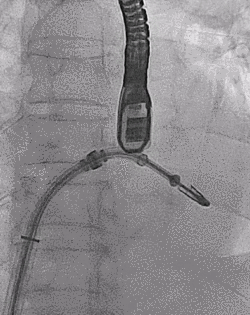

▲ MitraClip释放

患者全麻以后,在经食道超声心动图和X射线引导下,经股静脉入路,将MitraClip瓣膜夹顺利送至二尖瓣前后叶交界中心处,成功捕捉二尖瓣前叶A2和后叶P2,经超声心动图反复确认瓣叶夹持牢固后,测定有效夹持长度10.4mm,评估反流量降至轻度,释放瓣膜夹,超声心动图评估瓣膜夹位置和功能良好,测定左房压降至26/12mmHg,再次评估反流量仍为轻度,手术顺利完成。